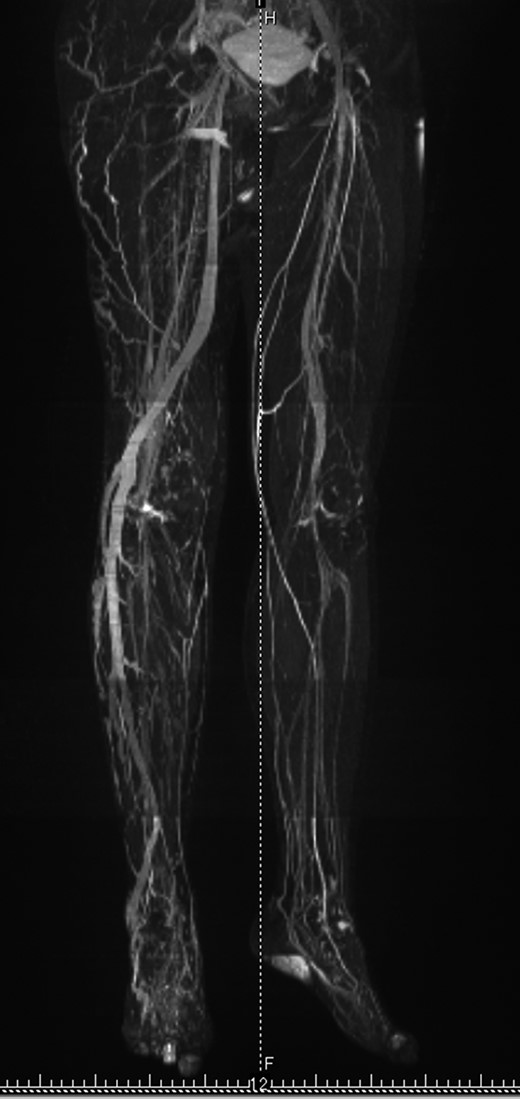

To rule out polyostotic type fibrous dysplasia, further questioning was done. Although she had not realized by herself, physical examination revealed that her right leg was longer than the other (Fig. 3a). Difference in circumferences was not obvious. Subcutaneous venous dilatation on the lateral side of her right leg was observed (Fig. 3b). Standing radiograph of the lower extremities showed leg length discrepancy of 31 mm (Fig. 4). In MRI venography (Fig. 5), vein with large caliber running from right lateral lower leg to great saphenous vein was observed. Venous density in the right leg was higher than the other, suggesting existence of venous malformation. The condition was diagnosed as Klippel–Trenaunay syndrome.

MRI venography of the lower extremities. Vascular density in the right leg is higher than in the left. Abnormally large calibered vessel runs from lateral part of the right lower leg to great saphenous vein.